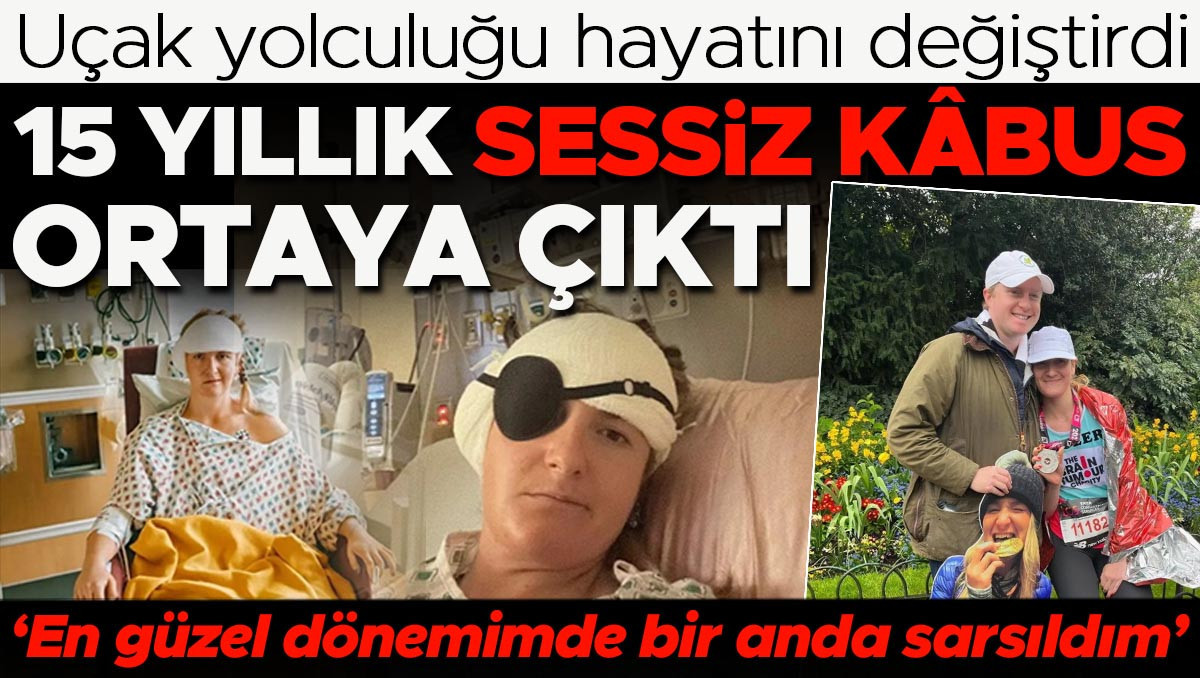

Yaşam

koycegiz-haber.com

Yaşam

koycegiz-haber.com

Yaşam

koycegiz-haber.com

Yaşam

koycegiz-haber.com